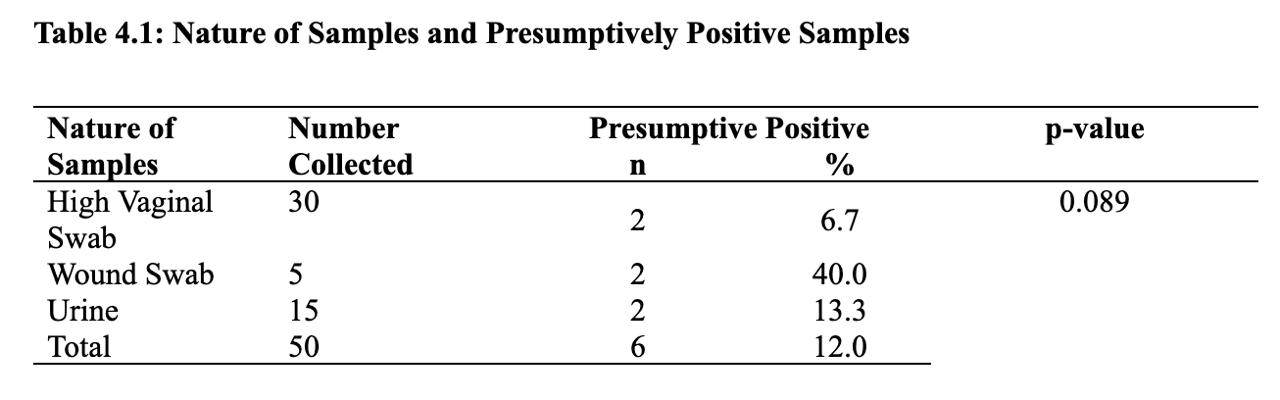

Prevalence of Carbapenemase Production in Pseudomonase Aeruginosa Isolates from Clinical Samples

Prevalence of Carbapenemase Production in Pseudomonase Aeruginosa Isolates from Clinical Samples